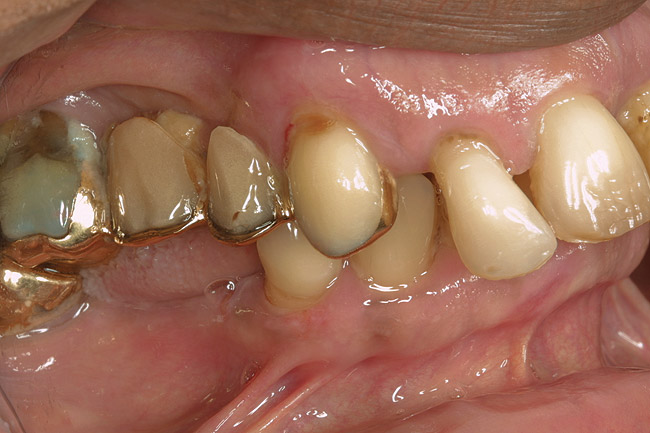

D2 root-surface lesions (Figure 3) are characterized by the dull surface demonstrated with D1 root-surface lesions. In addition, the surface feels sticky and somewhat soft when palpating with the side of the explorer. The examiner may notice that the root surface slightly resists gentle exploration over the root surface with the side of the explorer. Color changes in D2 root-surface lesions may range from dark yellow to orange/light brown. No cavitation of the root surface exists. The recommended treatment for D2 root-surface lesions includes remineralization with products (pastes and varnishes) containing fluoride, calcium, and phosphate. If the area is in the esthetic zone, the patient may request restoration, despite intact root structure.

It is common for practitioners to press the tip of the explorer into these root surfaces and decide to restore these “carious” areas. When pressing an explorer into a D2 root surface, a clinician may feel a definite softened surface or a “stick.” It is vital to either use the side of the explorer or visual inspection when determining these lesions. Aggressive exploration with the tip of the explorer may cavitate these root surfaces, which can lead to mechanical damage of the root surface and a decrease of the likelihood of successfully remineralizing the surface.

Figure 3  This root surface has a dull surface and is discolored. This indicates the progression of the demineralization/caries process. No cavitation has occurred due to this process. This root surface will feel slightly tacky and softened when exploring with the side of the explorer.

Figure 3